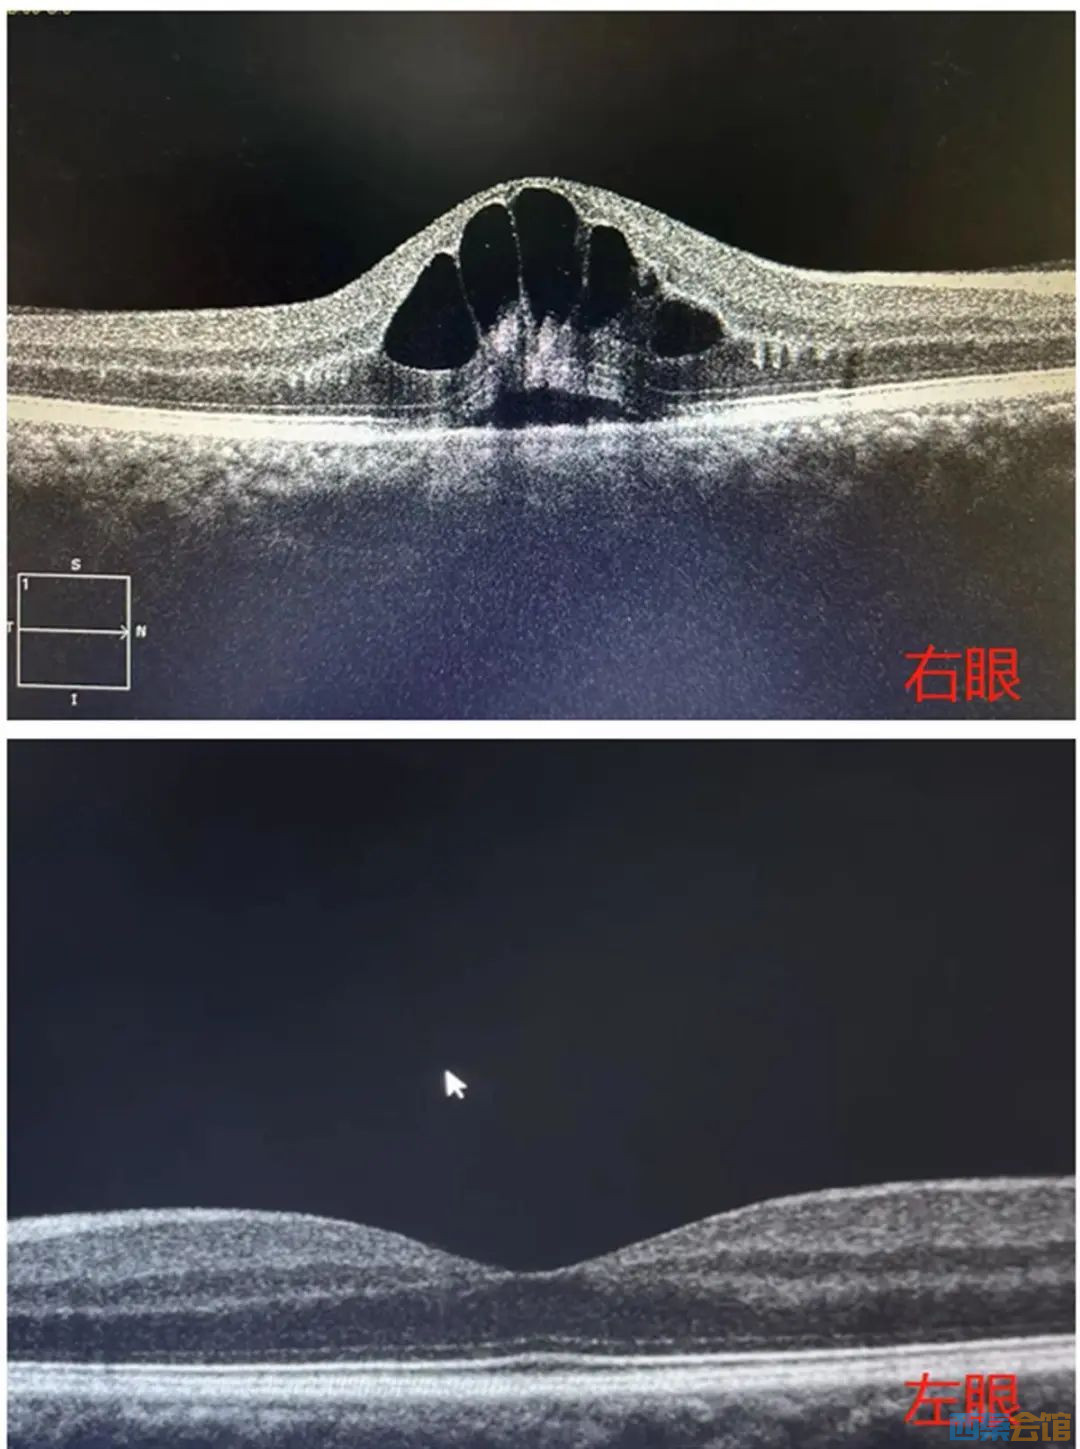

检查可见,眼底黄斑区出现“花瓣”状囊样水肿

上周开始,他发现自己右眼看东西有些模糊,想着最近忙于吃喝玩乐没有休息好,以为是视疲劳,并没有放在心上。9月28日,症状加重,刘先生才赶紧前往眼科医院就诊。经查,其右眼视力仅为0.3。进一步检查发现,刘先生眼底黄斑区出血及渗透,出现花瓣状囊样水肿,被诊断为“右眼视网膜静脉阻塞”。